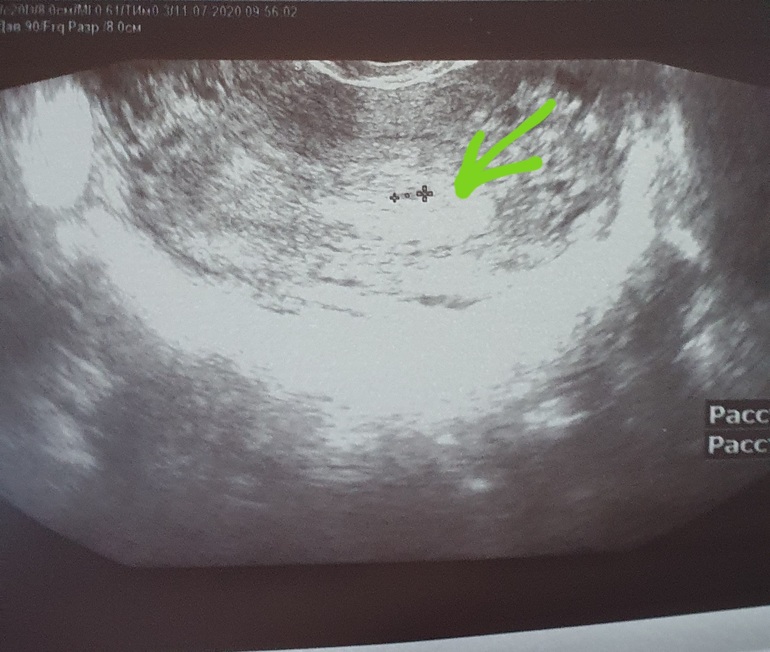

УЗИ сегодня 11.07. - что то очень маленькое и пока непонятное , эндометрий 17.

Я побежала потому , что у меня очень сильно болит низ живота справа, как оказалось О была в правом Я, слава богу опасения развеялись.. внематочной нет. За это я и переживала

А ну тогда понятно)) самое главное, что нашли что-то матке, пока крошечное 🥰 так как ХГЧ маленький. Все у вас хорошо 😊